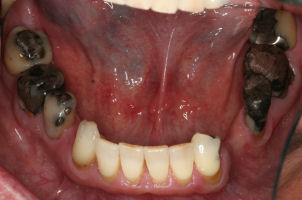

Before/After